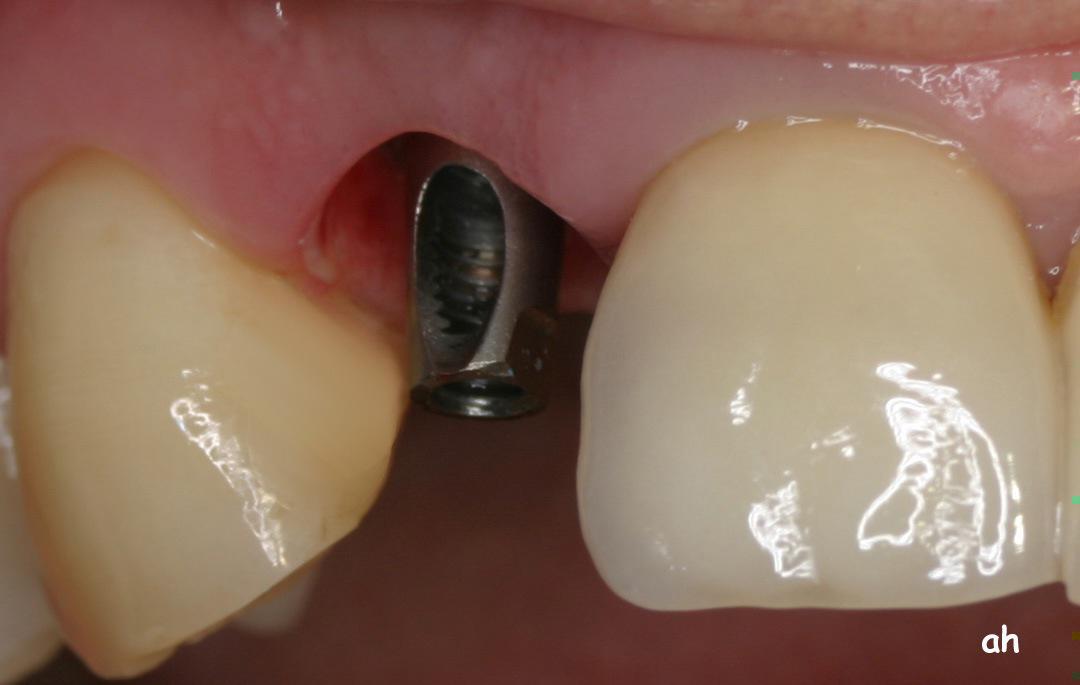

Exemple 3: Un implant à la place d'une incisive latérale supérieure droite. Sur cette image on voit le moignon en titane qui est vissé sur l'implant.

Exemple 3: Puis sur ce moignon, la couronne en céramique est scellée.

Exemple3: La couronne en place.